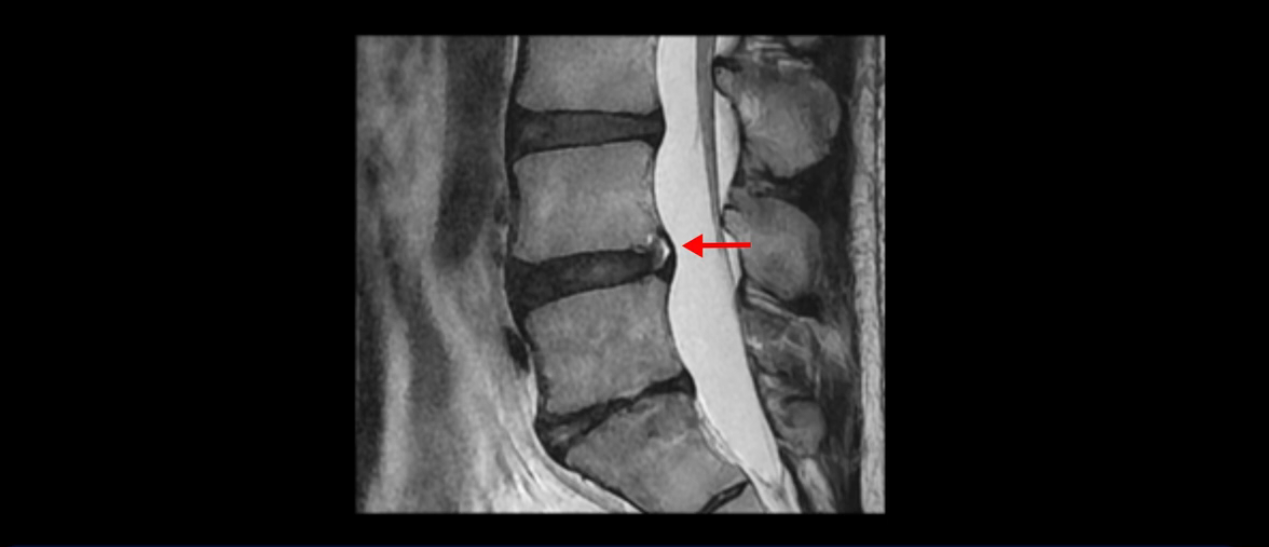

5번 1번 역시 가운데로 디스크 조금 밀려 나와있지만 신경 공간 넓이는 아주 넓어서 신경 눌림 있을 거라고 예상이 안됩니다.

앞서 1번 2번, 4번 5번, 5번 1번의 디스크가 찢어지고 조금 밀려 나온 게 최근에 찢어진 게 아니고 오래된 걸로 보인다고 말씀 드렸죠. 왜 그럴까요? 만약 급성으로 찢어진 것이라면 아주 심한 디스크성 통증이 있겠죠. 기침이나 재채기를 하면 심하게 아프고 허리를 조금만 구부리거나 비틀면 아주 날카로운 통증들이 생길 겁니다. 그런데 이분은 이런 증상이 전혀 아닙니다. 또 디스크의 밀려나온 정도도 전혀 심하지 않기 때문에 이분이 가지고 계신 양쪽 다리 저림, 특히 이분은 누워있을 때도 양쪽 발이 발가락까지 쑤신다고 하는데 이정도 디스크 때문에 그런 증상은 생길 수가 없는 겁니다. 이처럼 이분의 가벼운 디스크 탈출은 이미 오래 전에 진행되었고 섬유륜 자체는 이미 아문 상태인데도 디스크내장증을 진단받은 환자들 중에는 본인이 섬유륜 파열 환자라고 끝까지 믿는 분들이 많습니다. 다시 말하지만 디스크내장증이라는 진단을 받은 환자들을 보면 거의 전부 다 섬유륜 파열 증상이 아닙니다. 증상이 완전히 다릅니다. 진단이 애초에 잘못되면 어떤 치료를 받아도 좋아질 수 없습니다.